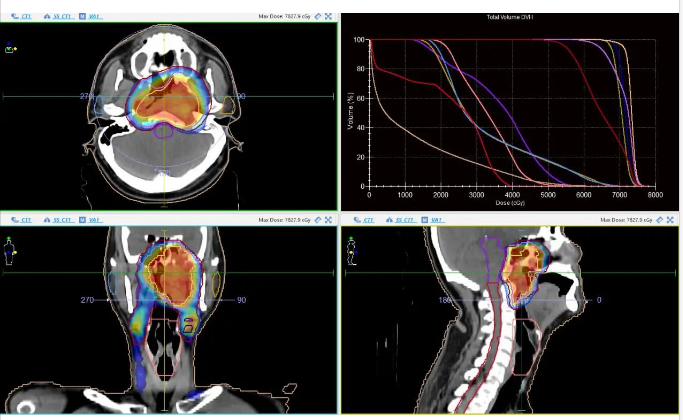

近年来,广东医附院肿瘤医院头颈部肿瘤专科通过放化疗、免疫、靶向等治疗方法和MRI-Sim、VMAT、肿瘤靶区自动勾画等先进放射治疗技术,致力于头颈部肿瘤患者的精准及个体化治疗,取得了良好的社会效益。头颈部肿瘤专科现有医生20人,护士15人,医生团队有博士6人,在读博士3人,博士研究生导师1人,博士后合作导师2人,硕士研究生导师5人,双师型人才1人。医生团队有正高4人,副高8人,中级3人,初级5人。

科室技术力量雄厚,医生们经过国内外大肿瘤中心的专科系统性培训,在鼻咽癌、头颈部鳞癌、神经肿瘤的诊治领域有深入的研究及独特的见解,尤其在鼻咽癌个体化治疗和适形调强放疗方面形成了一整套科学有效并独具特色的治疗规范,鼻咽癌的系列研究成果获得2023年广东医学科技奖三等奖和2023年“创新湛江”科学技术奖二等奖(均为第一完成单位)。